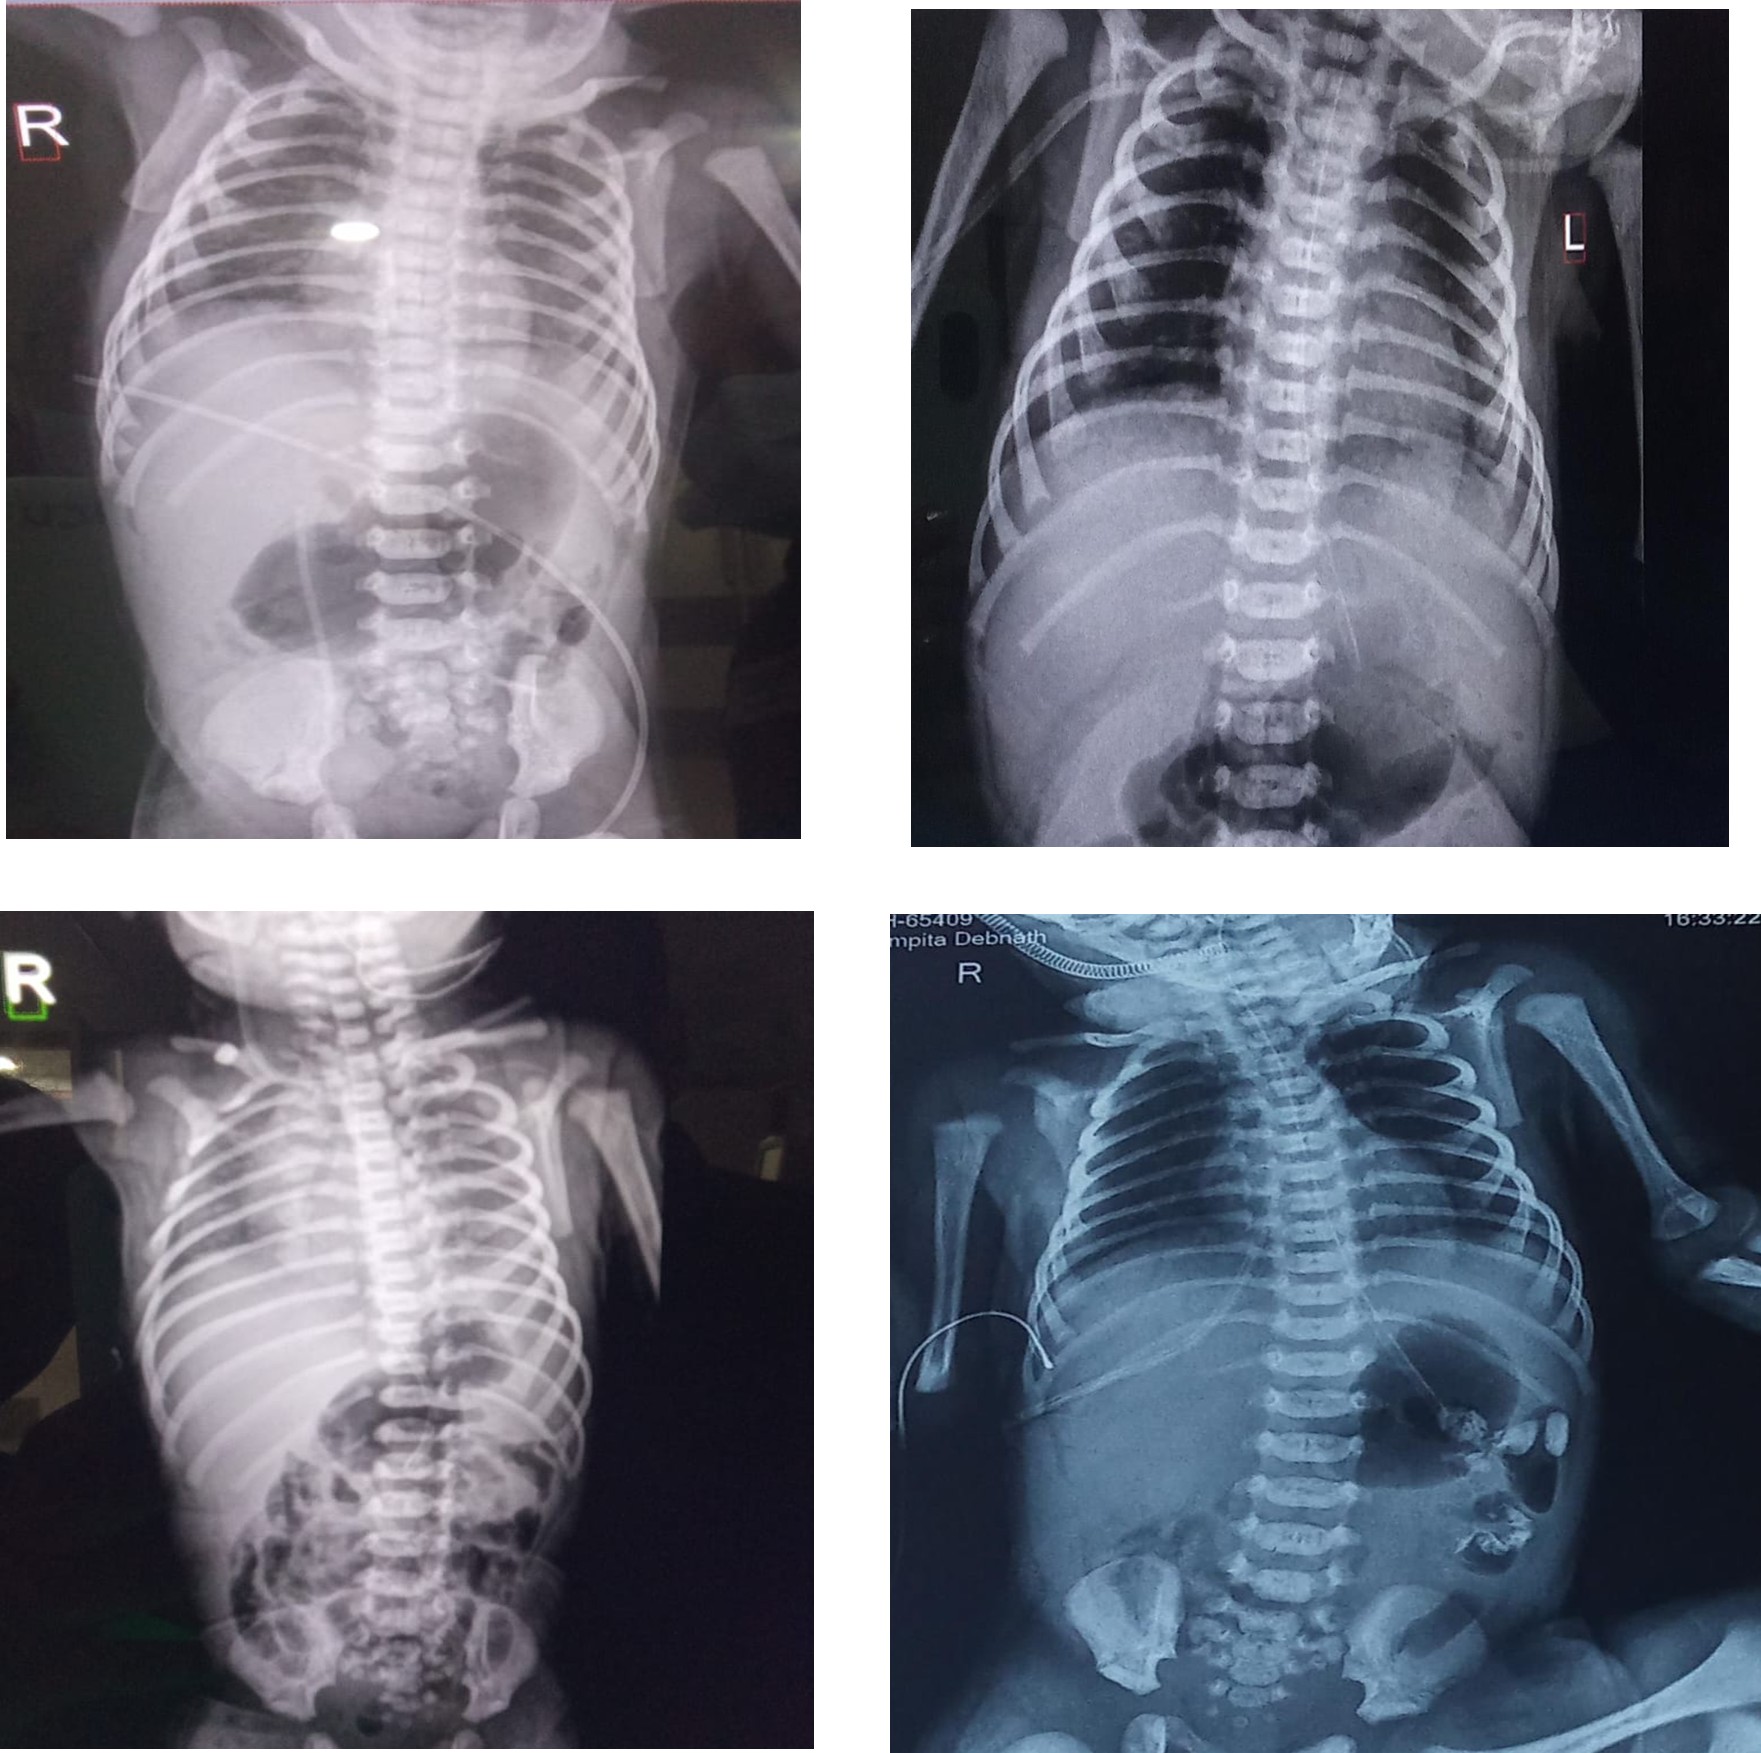

At approximately 12 hours of life, the neonate developed respiratory distress. Chest X-ray revealed heterogeneous pulmonary opacities without hyperinflation. High-flow nasal cannula (HFNC) support was initiated at 5 L/min with FiO₂ 25 %. HFNC continued for 7 days, then weaned to low-flow support and finally to room air by day 9. Intravenous AUGMENTIN and Amikacin were administered; blood culture was sent.

4. Midgut Malrotation (Surgical Condition)

As feeds advanced, the baby developed tachypnea and bile-stained gastric aspirates. From 30 hours, feeds were withheld (NPO). Sepsis markers were elevated (CRP 4.1 mg/dL) and antibiotics were escalated, but bilious aspirates persisted. Abdominal ultrasonography suggested malrotation, and a contrast study confirmed obstruction. On day 4 of life, emergency exploratory laparotomy was performed. Midgut malrotation was identified; de rotation and Ladd’s procedure were successfully completed. Postoperatively, the baby remained NPO for 3 days and received glucose infusion and amino acid nutrition. Enteral feeds were restarted on postoperative day 3 and advanced gradually to full feeds by day 12.

Meconium Aspiration Syndrome and Respiratory Outcome

Midgut malrotation often presents with non-specific symptoms in the neonatal period and may be masked by concurrent systemic illnesses such as sepsis or respiratory distress. In this case, the initial emphasis on respiratory and metabolic stabilization had the potential to delay recognition of the underlying surgical pathology. However, the persistence of bilious gastric aspirates associated with progressive abdominal distension, even during nil per oral status, served as a critical red-flag sign. Early imaging with abdominal ultrasonography followed by contrast study enabled timely diagnosis and intervention. This reinforces that bilious aspirates with abdominal distension in neonates should be treated as a surgical emergency until proven otherwise.